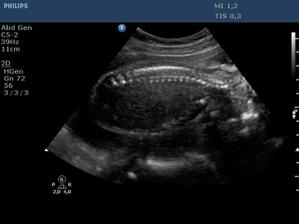

Ultrazvuk miminka - 24 týden

Z "menší protekce" u pana primáře Radiodiagnostického oddělení jsme mohli na soukromou "špionáž" naší krásné holčičky... (Pan doktor je už třetí, kdo hádá holčičku a po pravdě s tím přístrojem, co má k dispozici, bylo naprosto zřetelně vidět, že tam žádný pytlík není! :o)) Natočil nám i několik videí, kde ta naše šibalka zívala a dvakrát na nás dokonce vyplazovala jazyk. ;o)